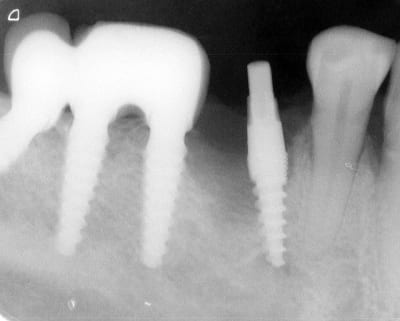

Bonjour flicflac je suis désolé de ma réponse tardive, oui il est vrai que ce n est pas beaucoup documenté ... je serai un menteur de dire que que je n ai jamais perdu des implants, surtout entre la 2eme et 8eme semaine après l implantation.Un échec vraiment à cause de la perte osseuse et avec le même process cela est arrivé une fois avec une madame, où l´os était encore infecté ( avant la chirurgie),mais après l ´échec (c était à la position 35) on a pu laisser le bridge. Malheureusement je n ai pas toutes les photos ici à Mallorque sur mon PC portable. Ci dessous une photo après 10 ans 46 47 et les implants au maxillaire.

Oui ca semble ....sur la opg radio tu peux voir la situation seulement deux semaines après l´implantation immédiate 34 jusqu´à 36 et 45, les derniers 2 photos montrent la même situation après un an ( où on a enlevé la supra construction pour un contrôle). Sur ce cas je voulais montrer la bonne régénération osseuse et de la gencive.